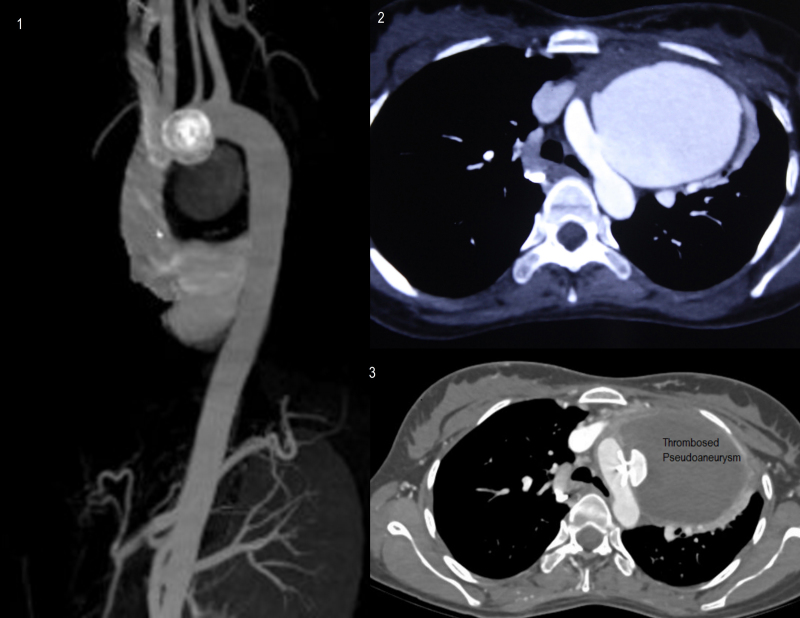

Fig. 3.

(1) Reconstructed follow-up computed tomography (CT) aortogram at one month revealing complete sealing of communication between aorta and pseudoaneurysm. (2) Preprocedure CT contrast image showing opacification of aorta and pseudoaneurysm with communication (arrows). (3) Follow-up CT contrast image showing opacification of aorta, device and nonopacification and thrombosis of pseudoaneurysm.

She was on anti-tuberculous therapy for the treatment of tuberculous pericardial effusion since 5 months which included 3 months of five-drug regimen (streptokinase, isoniazid, rifampicin, pyrazinamide, and ethambutol) and was currently receiving two drugs (isoniazid and rifampicin). Her serial chest X-rays revealed homogenous opacity from left hilum extending into left upper lobe of the left lung which had increased in size over a period of four months. Her echocardiography revealed dilated right atrium and right ventricle secondary to external compression of the main pulmonary artery. There was peak gradient of 58 mmHg across compressed main pulmonary artery. On further investigation with a CT scan it was found that she had a pseudoaneurysm arising from the undersurface of the aortic arch originating opposite to the origin of the right subclavian artery (Fig. 1). This aneurysm was extending up to the sternum. Echo review suggested a communication neck measuring 9 mm between arch of aorta and aneurysm (Fig. 1).

Fig. 1.

(1) Echocardiography showing communication between aorta (A) and pseudoaneurysm (B) with well-defined margins. (2) Computed tomography (CT) scan of thorax with contrast revealing large pseudoaneurysm arising from arch of aorta, extending anteriorly up to sternum. (3) CT scan of thorax with contrast revealing large pseudoaneurysm seen compressing main pulmonary and right pulmonary artery. (4) CT scan of thorax with contrast revealing large pseudoaneurysm arising from arch of aorta occupying left upper side of thorax.